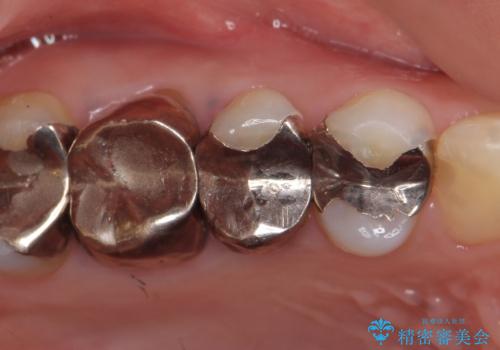

検査の結果右上5の歯の神経が死んでいたため、根管治療を行った後に、オールセラミッククラウンによる補綴を行いました。

また右上6に関しては再根管治療を行い、右上4に関しては虫歯治療を行った後に、オールセラミッククラウンによる補綴を行いました。